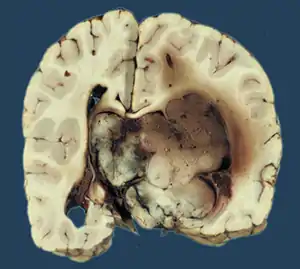

Choroid plexus papilloma, also known as papilloma of the choroid plexus, is a rare benign neuroepithelial intraventricular WHO grade I lesion found in the choroid plexus.[1] It leads to increased cerebrospinal fluid production, thus causing increased intracranial pressure and hydrocephalus.[2]

Choroid plexus papilloma occurs in the lateral ventricles of children and in the fourth ventricle of adults. This is unlike most other pediatric tumors and adult tumors, in which the locations of the tumors is reversed. In children, brain tumors are usually found in the infratentorial region and in adults, brain tumors are usually found in the supratentorial space. The relationship is reversed for choroid plexus papillomas.

Choroid plexus papillomas are benign tumors that are usually cured by surgery; malignant progression has been rarely reported.